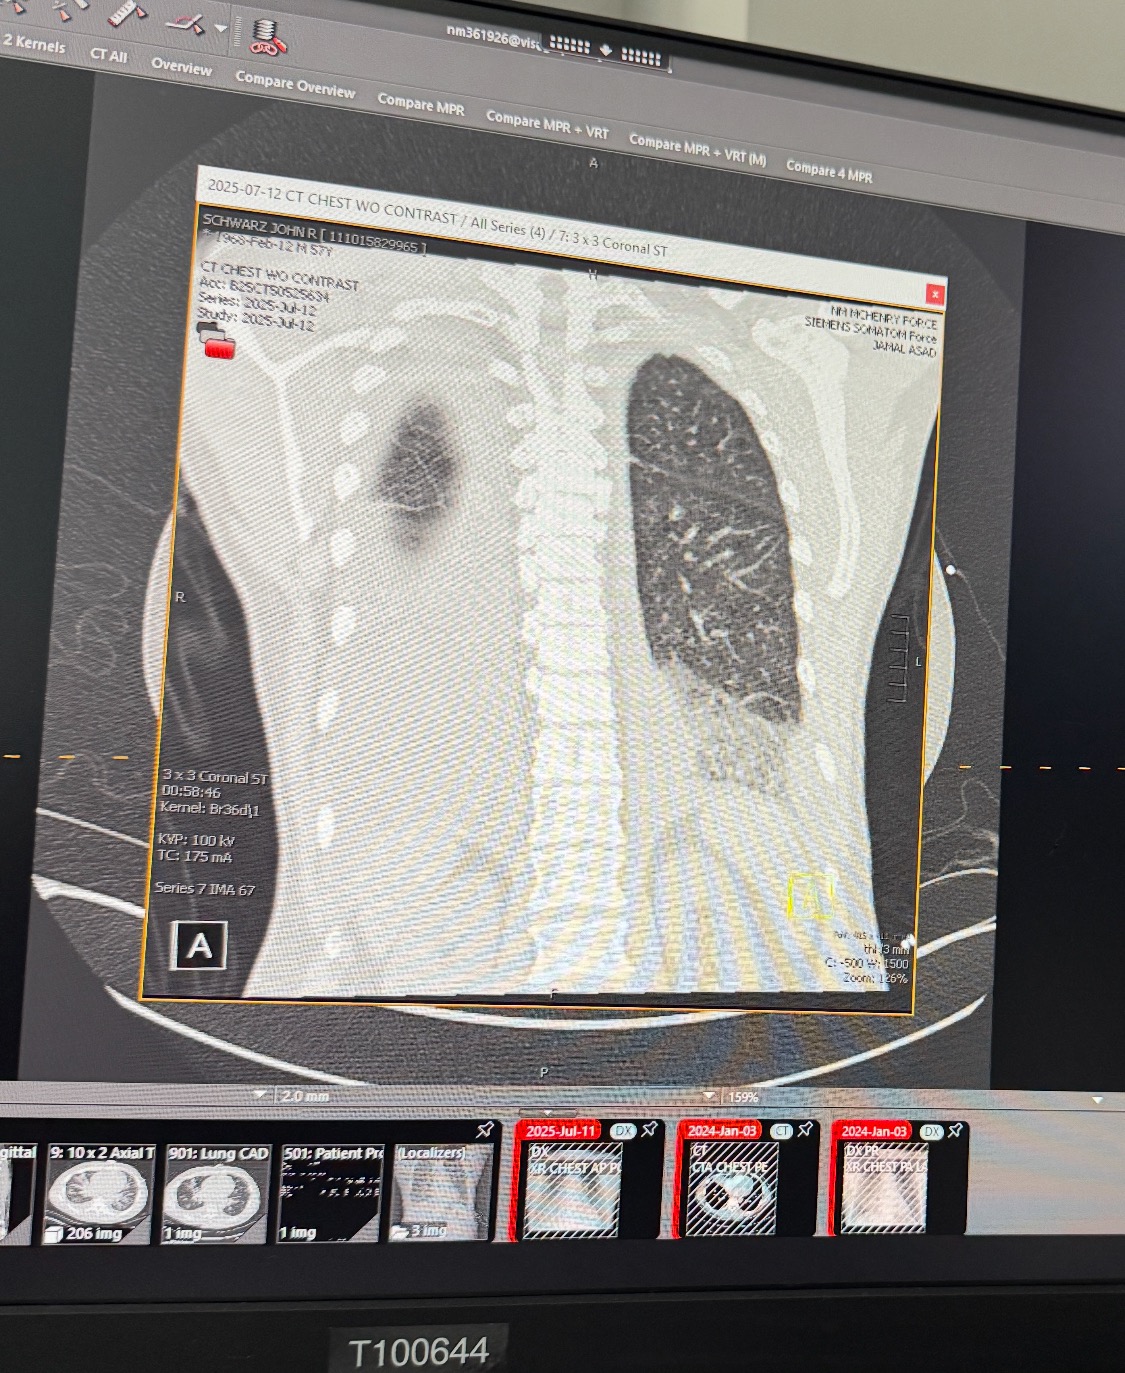

What started as a frightening medical emergency has now become a full life reset. Over the past several weeks, I’ve undergone a whirlwind of major procedures, a thoracentesis to drain fluid from my lungs, an angiogram, a cardioversion, and just recently, a cardiac ablation to help correct the atrial fibrillation that had taken hold of my heart, and of course living with Congestive Heart Failure.

This all came after being diagnosed with congestive heart failure and pneumonia in both lungs, and it’s forced me to fully stop and focus on healing, physically, emotionally, and spiritually.